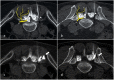

Low back pain (LBP) is the most common pain syndrome, and is an enormous burden and cost generator for society. Lumbar facet joints (FJ) constitute a common source of pain, accounting for 15-45% of LBP. Facet joint degenerative osteoarthritis is the most frequent form of facet joint pain. History and physical examination may suggest but not confirm facet joint syndrome. Although imaging (radiographs, MRI, CT, SPECT) for back pain syndrome is very commonly performed, there are no effective correlations between clinical symptoms and degenerative spinal changes. Diagnostic positive facet joint block can indicate facet joints as the source of chronic spinal pain. These patients may benefit from specific interventions to eliminate facet joint pain such as neurolysis, by radiofrequency or cryoablation. The purpose of this review is to describe the anatomy, epidemiology, clinical presentation, and radiologic findings of facet joint syndrome. Specific interventional facet joint management will also be described in detail. TEACHING POINTS: • Lumbar facet joints constitute a common source of pain accounting of 15-45%. • Facet arthrosis is the most frequent form of facet pathology. • There are no effective correlations between clinical symptoms, physical examination and degenerative spinal changes. • Diagnostic positive facet joint block can indicate facet joints as the source of pain. • After selection processing, patients may benefit from facet joint neurolysis, notably by radiofrequency or cryoablation.